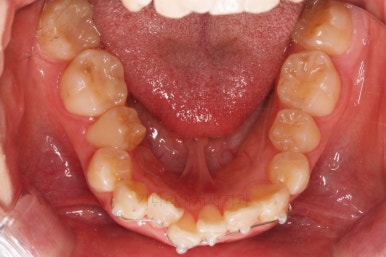

아랫니가 매우 밑으로 많이 내려온게 보이시죠?

과개교합은 비교적 초반에 개선이 되었습니다.

아래 앞니의 높이가 개선된 뒤, 아랫니도 가지런하게 해줍니다.

윗니도 어느새 치아를 뽑은 공간이 많이 줄었네요.